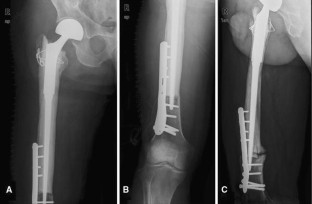

Fig. 1